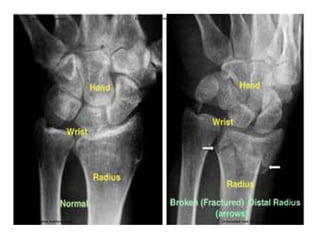

El documento describe la anatomía del antebrazo y la mano. Explica que el antebrazo está formado por el radio y el cúbito, describiendo las características de cada hueso como sus cuerpos, extremidades y superficies articulares. También describe la articulación del codo y los huesos de la mano, incluyendo el carpo, los metacarpianos y las falanges.